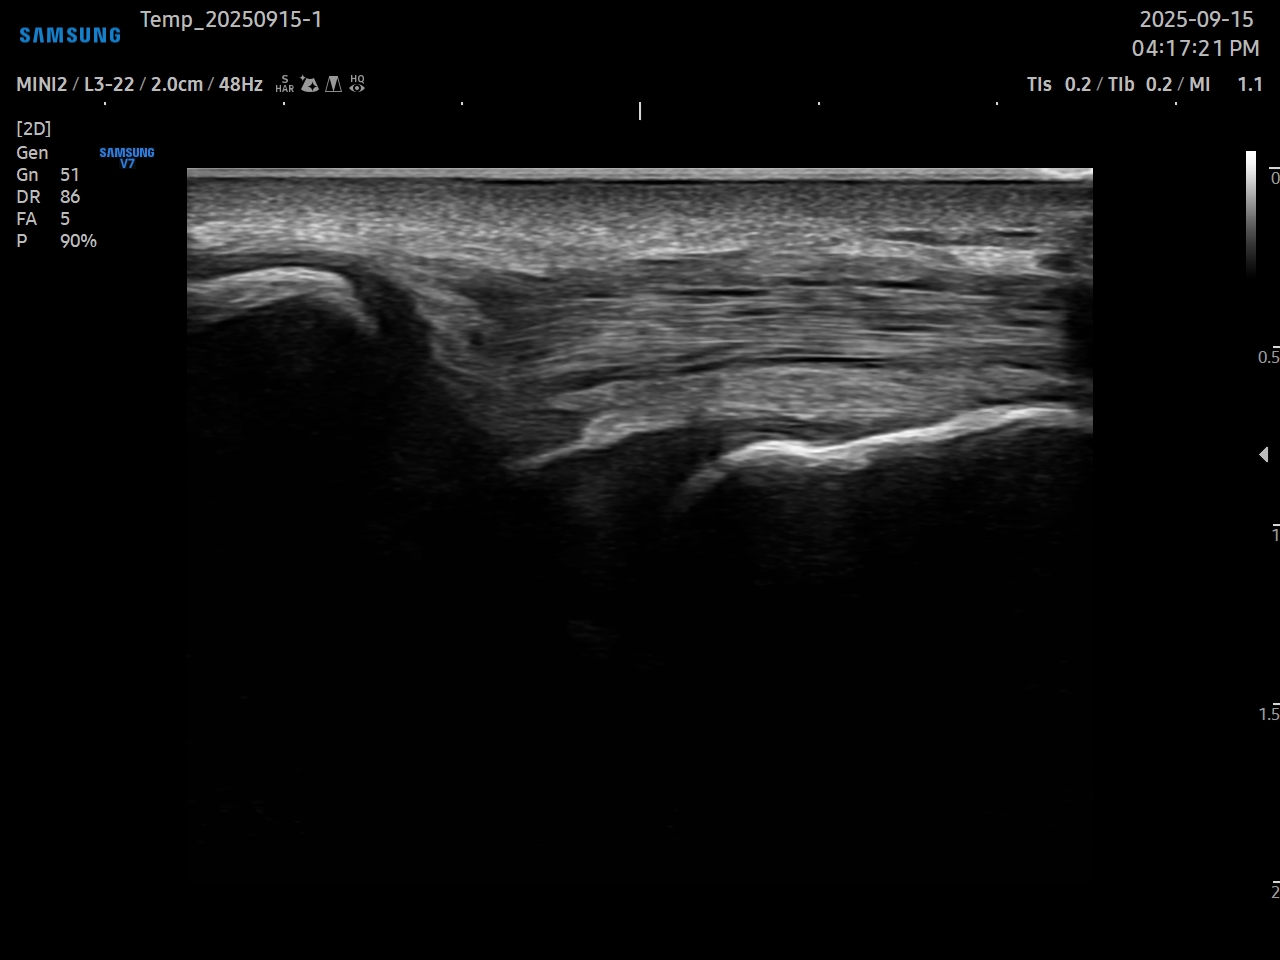

초음파 약침 치료를 통해 척추관협착증 증상을 개선한 사례

척추관협착증, 80대 여성